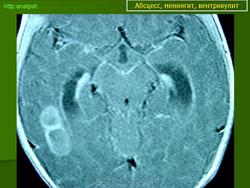

Абсцесс головного мозга – это очаговое скопление гноя в мозговом веществе, окруженное капсулой.

Абсцессы могут локализоваться в различных участках мозгового вещества. Обычно абсцессы сочетаются с менингоэнцефалитами, энцефалитами, сопровождаются повышением температуры тела, воспалительными изменениями крови и ликвора. Клиническая картина разнообразна и состоит из различных сочетаний общемозговых симптомов (головной боли, головокружения, тошноты, рвоты, нарушений сознания), менингеальной (оболочечной) и очаговой неврологической симптоматики.

Компьютерная (КТ) или магнитно-резонансная (МРТ) томография головного мозга являются ведущими методами диагностики посттравматических абсцессов, позволяющих судить об их расположении, объеме, структуре, консистенции, содержимом, воздействии на вещество головного мозга. Для исключения опухолей головного мозга, туберкулом, паразитарных заболеваний проводится ОФЭКТ (однофотонная эмиссионная компьютерная томография).